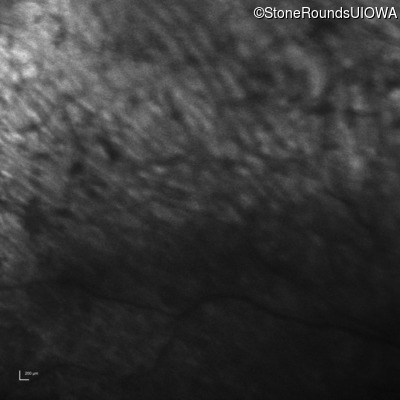

Infrared Fundus Photograph - Left - Hand Motion sc

Exemplar